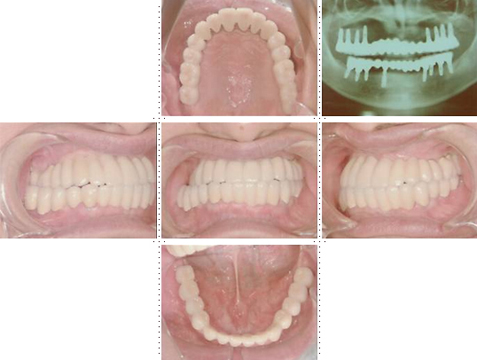

症例1

58才 女性

嘔吐反応が激しく入れ歯を入れると気持ち悪くなってしまうと、インプラント希望で来院されました。

上顎左右奥に4本ずつ計8本のインプラント埋入。下顎左右奥に3本ずつ計6本のインプラント埋入上下顎とも全体的にセラミックを使用した冠をセット。